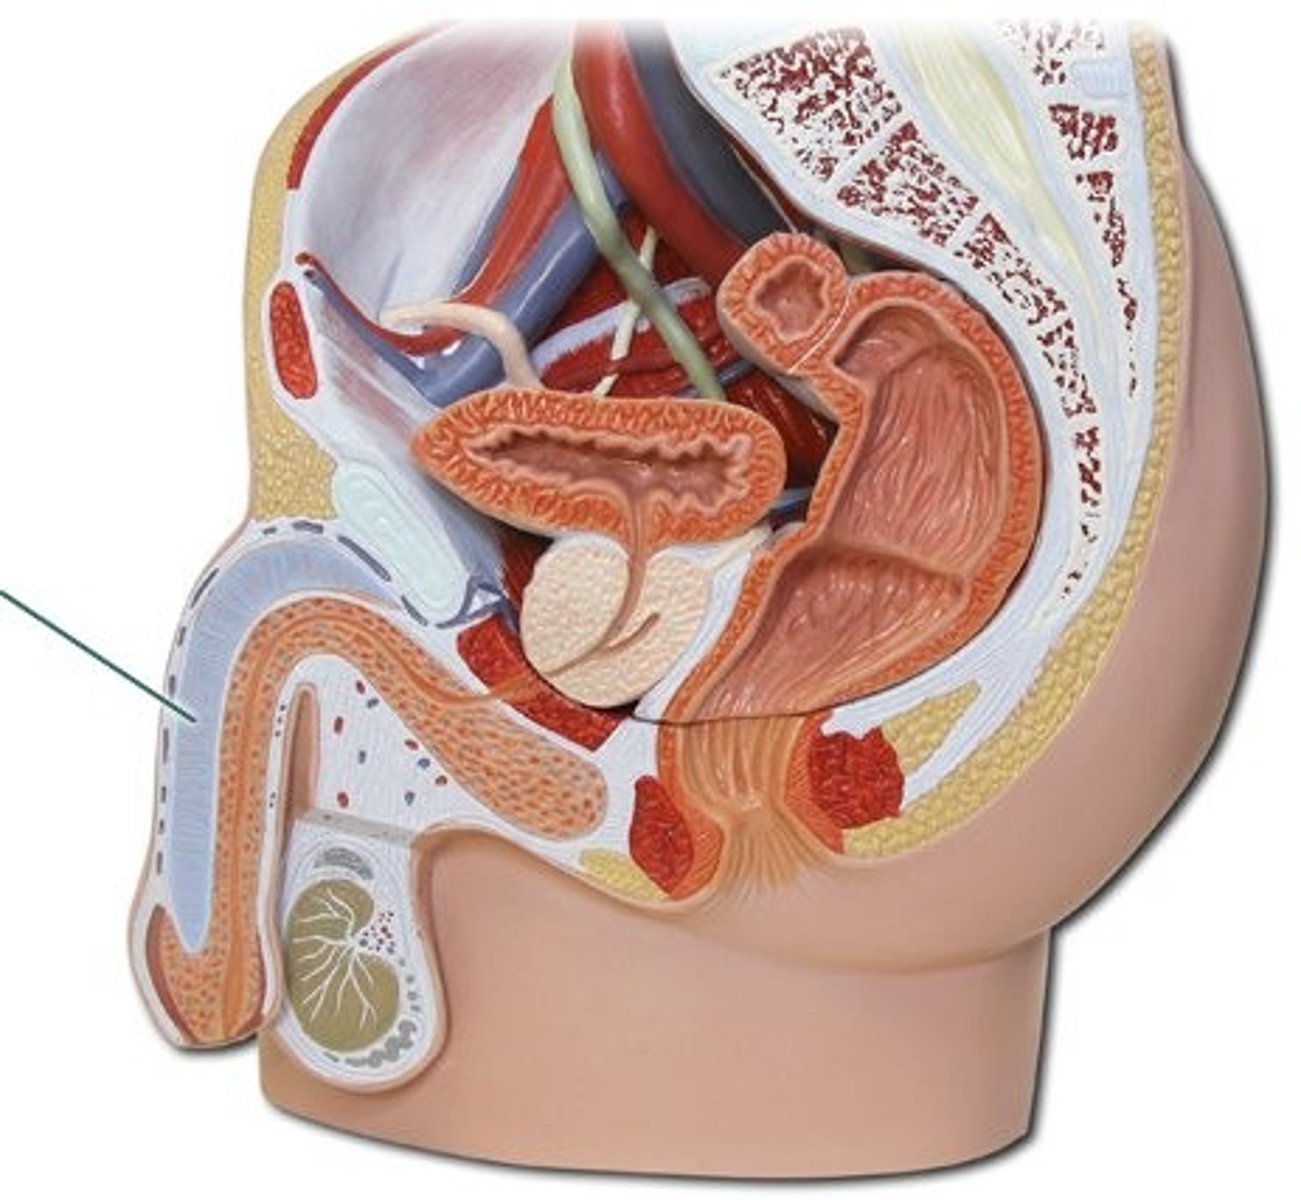

Spermatic cord

Ductus deferens

Ampulla (ductus deferens)

Ejaculatory duct

Seminal gland

Prostate gland

Bulbourethral gland

Urethra

Urethra

Prostatic urethra

Membranous urethra

Spongy urethra

Penis